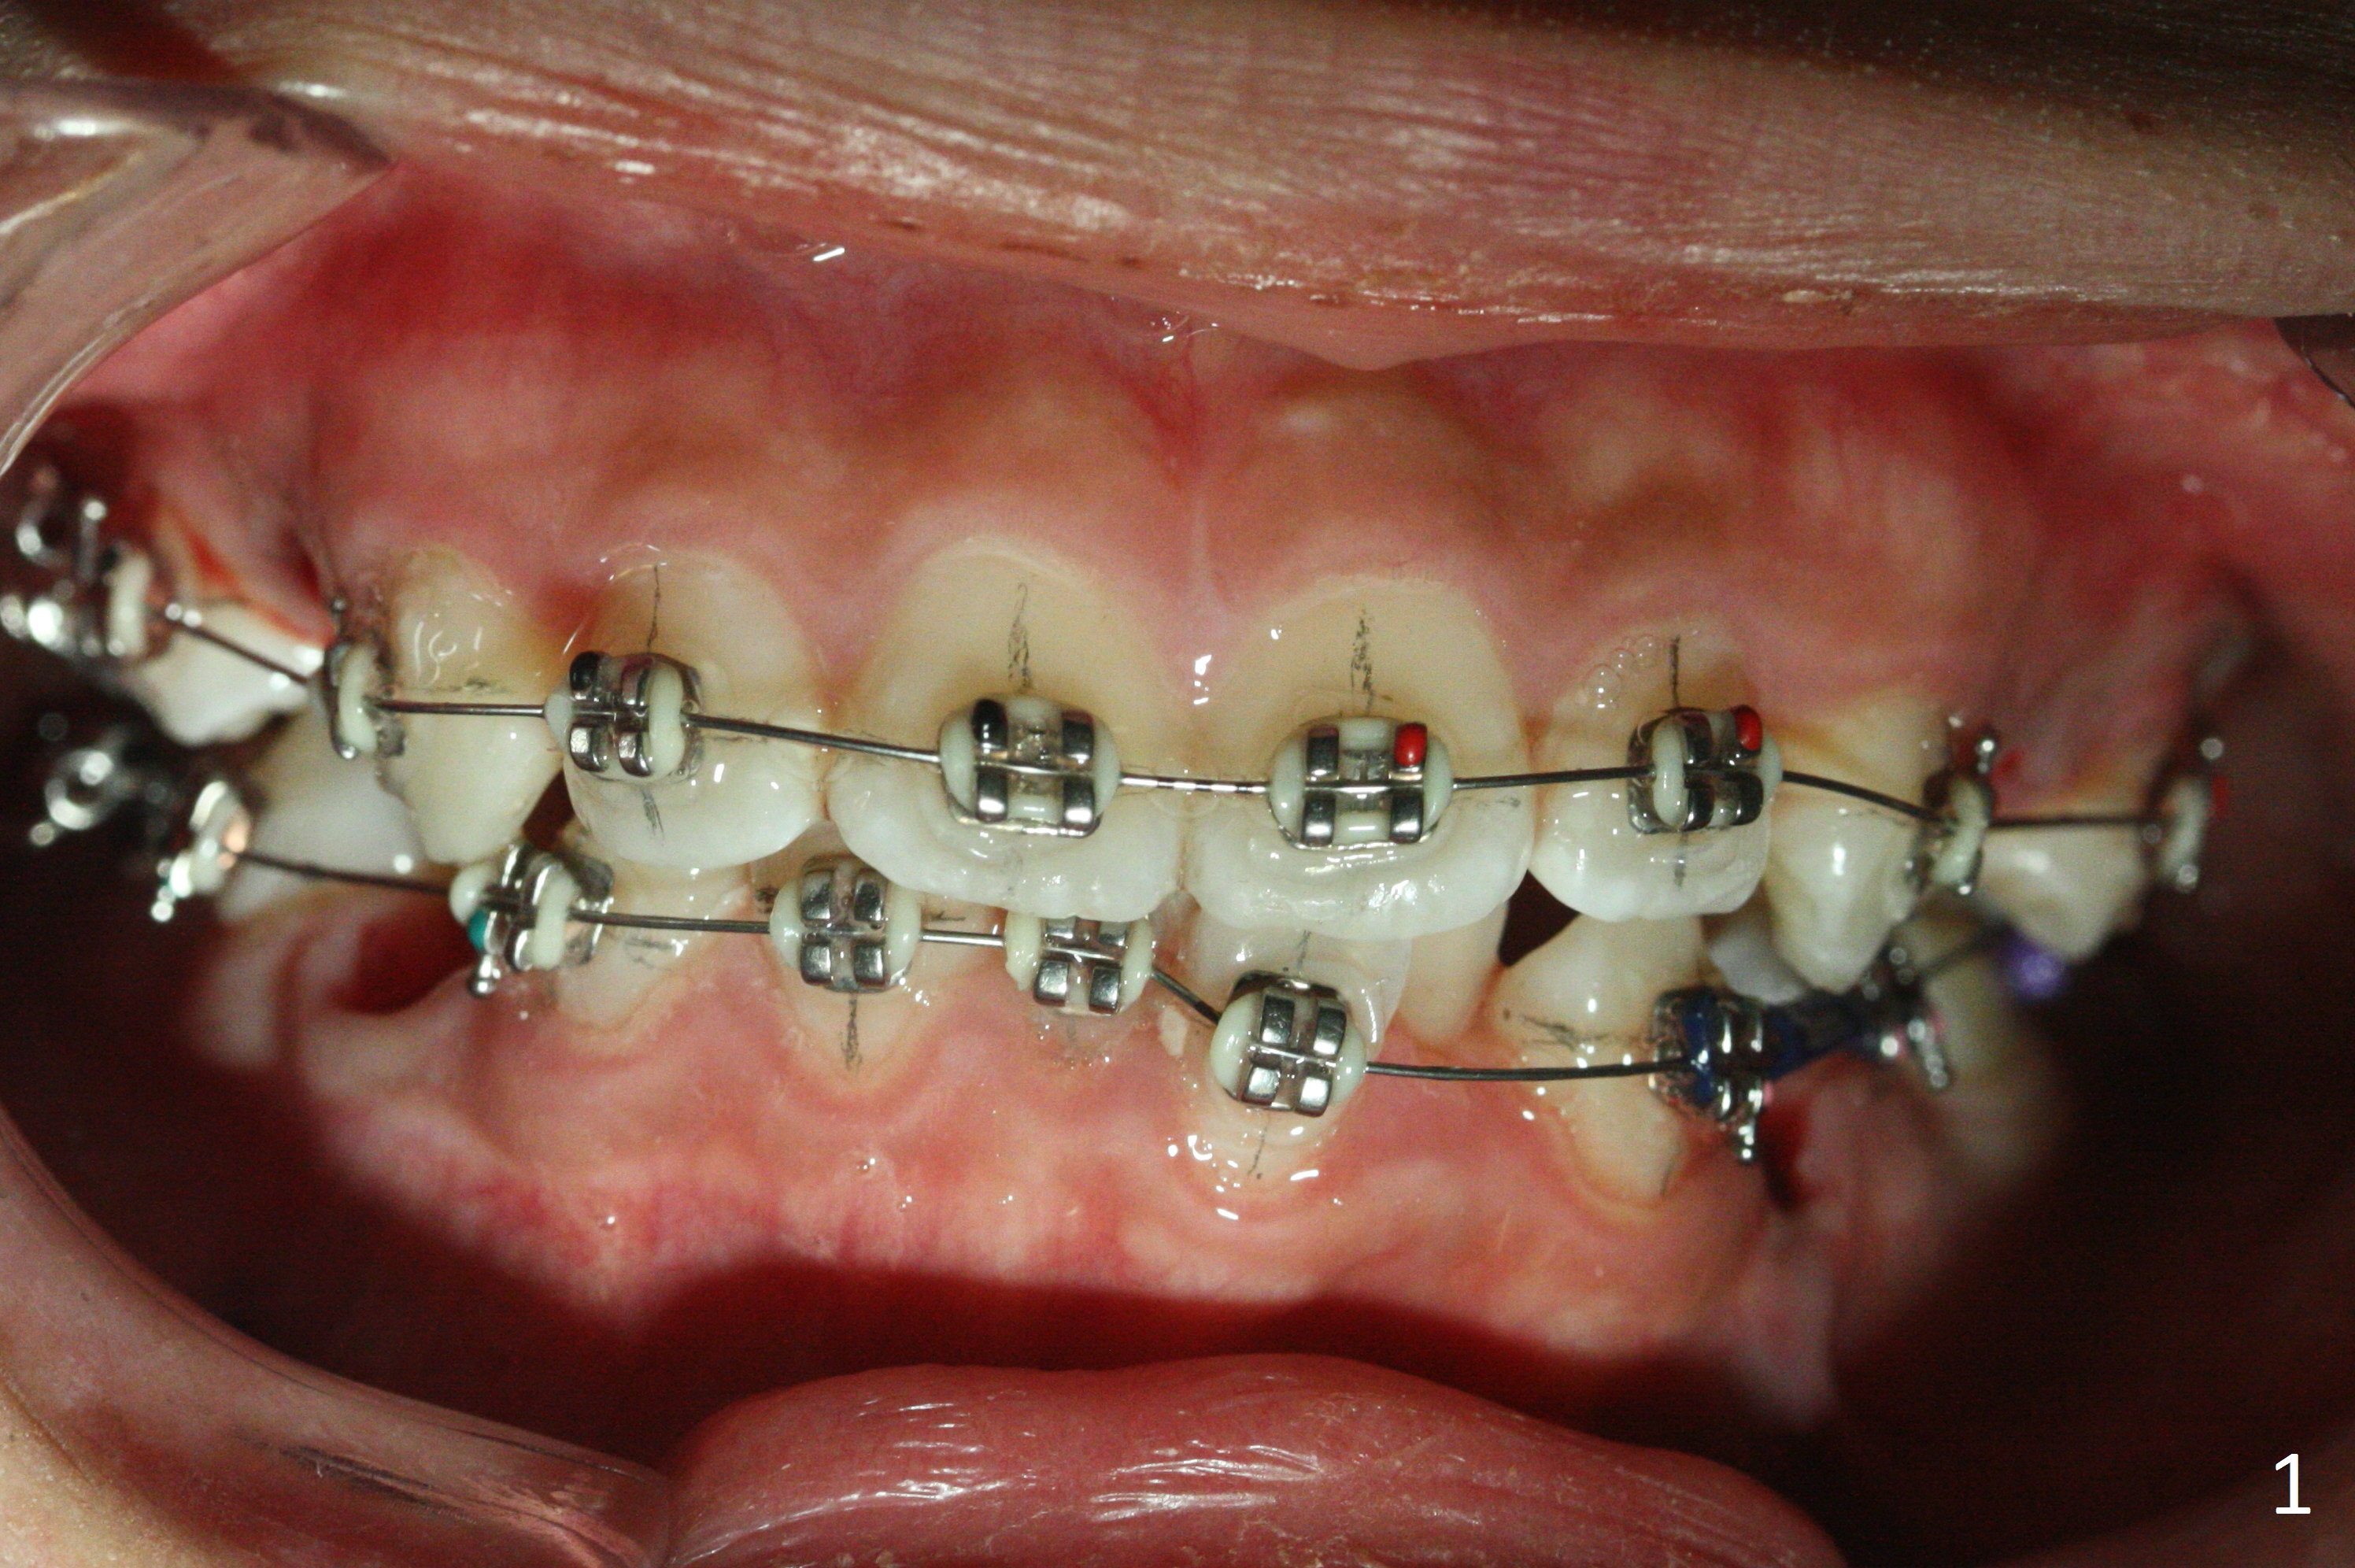

When the 17-year-old woman returns for banding, she has no problem with extraction (Fig.1). Since UL5 is buccally displaced, it is extremely difficult to insert .012 niti wire into the 1st molar band when the lower tube slot is smaller (apparently .018 instead of .022, Fig.2). Do not remove the thin niti wire before the bicuspid is linguolized.

In fact there is enough space for banding at LL6 with reuse of 12 niti (Fig.4). Anterior crowding improves 1 month post banding (Fig.5, as compared to Fig.1-3); there is no difficulty in place 14 niti wire between UL 5 and 6 (Fig.6, as compared to Fig.3), since UL5 has been lingualzied.